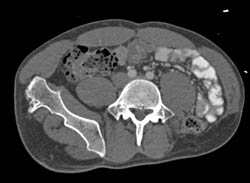

Incidental Soft Tissue Mass in Gluteal Muscle